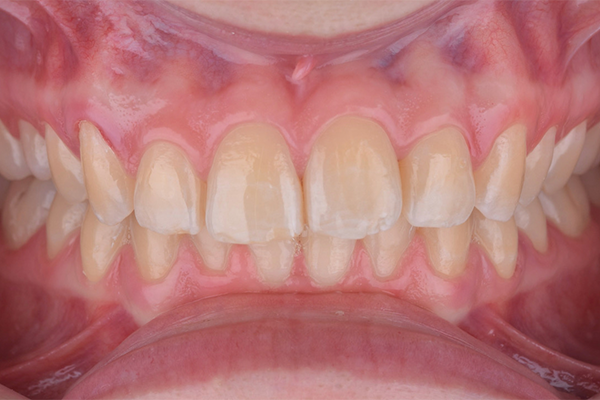

1 | Sorriso inicial, vista frontal.

2 | Aspecto inicial, intraoral.